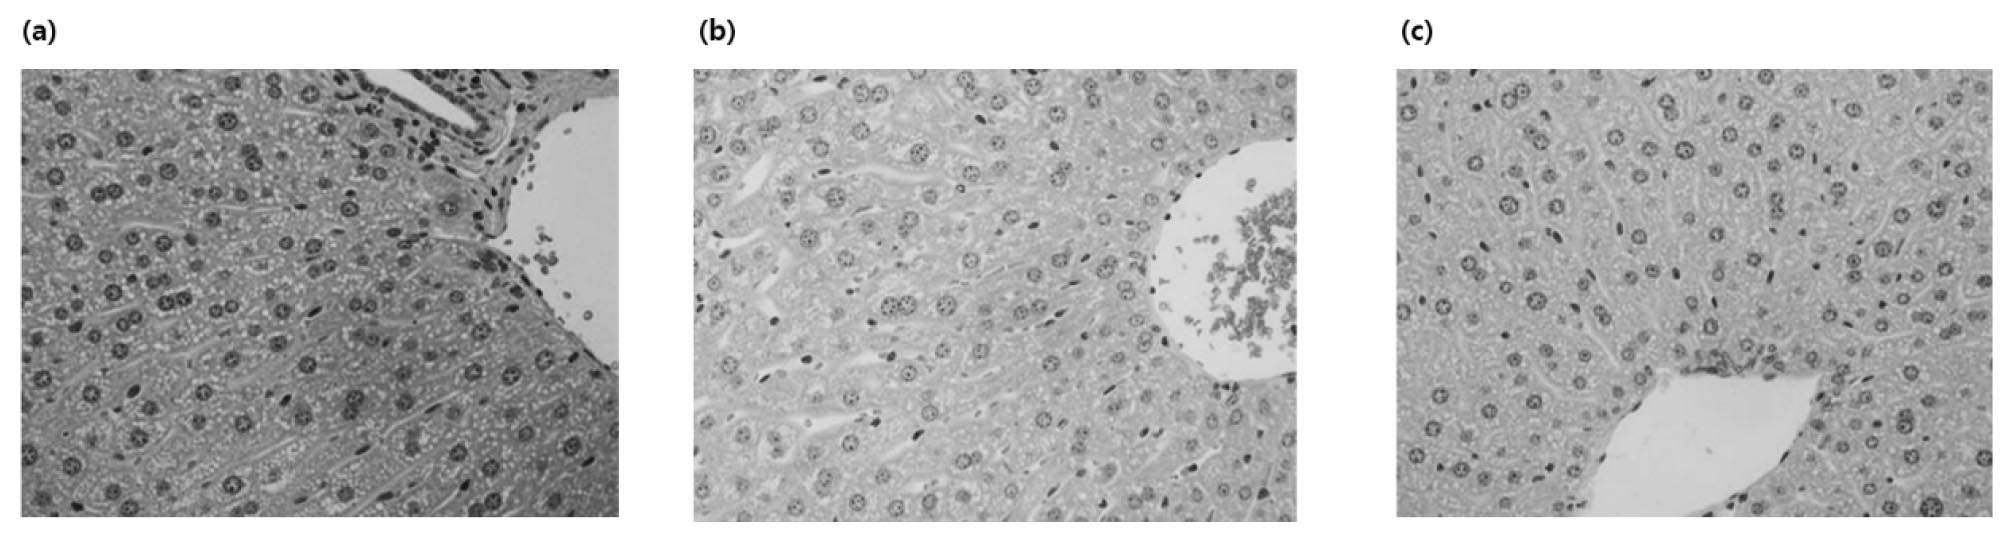

Eight-week-old male C57BL/6 mice were orally administered once daily for four weeks with 3 ㎎/㎏ body weight of alcohol. When hepatocytes are damaged, enzymes present in hepatocytes are released into the blood, and blood levels increase (Fig. 4, Fig. 5). These enzymes and indicators serve as indicators representing the degree of liver damage. As a result of measuring AST and ALT activities in plasma, ALT and AST activities were significantly increased in the alcohol- administered group compared to the normal diet group, confirming that liver tissue was effectively damaged by alcohol. To verify the effects of Alnus 25, Purslane 25, and Complex 50 on alcohol metabolism, which were confirmed by the improvement of acute alcoholic liver damage, the improvement effect on chronic alcoholic liver damage was confirmed (Table 2). In AST and ALT, liver function indices, the Alnus complex showed better physiological activity than Alnus and purslane alone, and A. japonica extract showed a superior LDH reduction effect. CAT activity measured in liver tissue was confirmed to be more effective in the purslane extract than in the A. japonica extract, and in particular, it was confirmed that the ALPOC exhibited the most excellent antioxidant effect (Fig. 4). The state of the liver tissue was established through H&E staining of the liver tissue (Fig. 6). Cell nuclei in the liver tissue were observed in the normal diet group, but many necrosis and hemorrhage were observed in the alcohol-treated group. On the other hand, it was confirmed that necrosis and hemorrhage were reduced in the complex administration group.

In chronic alcoholic liver damage, it was confirmed that ALT showed an improvement effect of 25% or more when a high dose of the complex was ingested. AST showed an improvement effect similar to that of the positive control, Hovenia 100 extract. In addition, through H&E staining analysis, it was observed that necrosis and hemorrhage caused by liver damage were improved by the ALPOC. In terms of the change in catalase, an antioxidant index, the low-dose group of ALPOC showed vigorous antioxidant activity of 127 % or more compared to the alcohol intake group, which was confirmed to offer a very high activity exceeding 20% or more than that of Hovenia extract. On the other hand, there was no significant difference in LDH activity in plasma between the Hovenia extract and the groups.